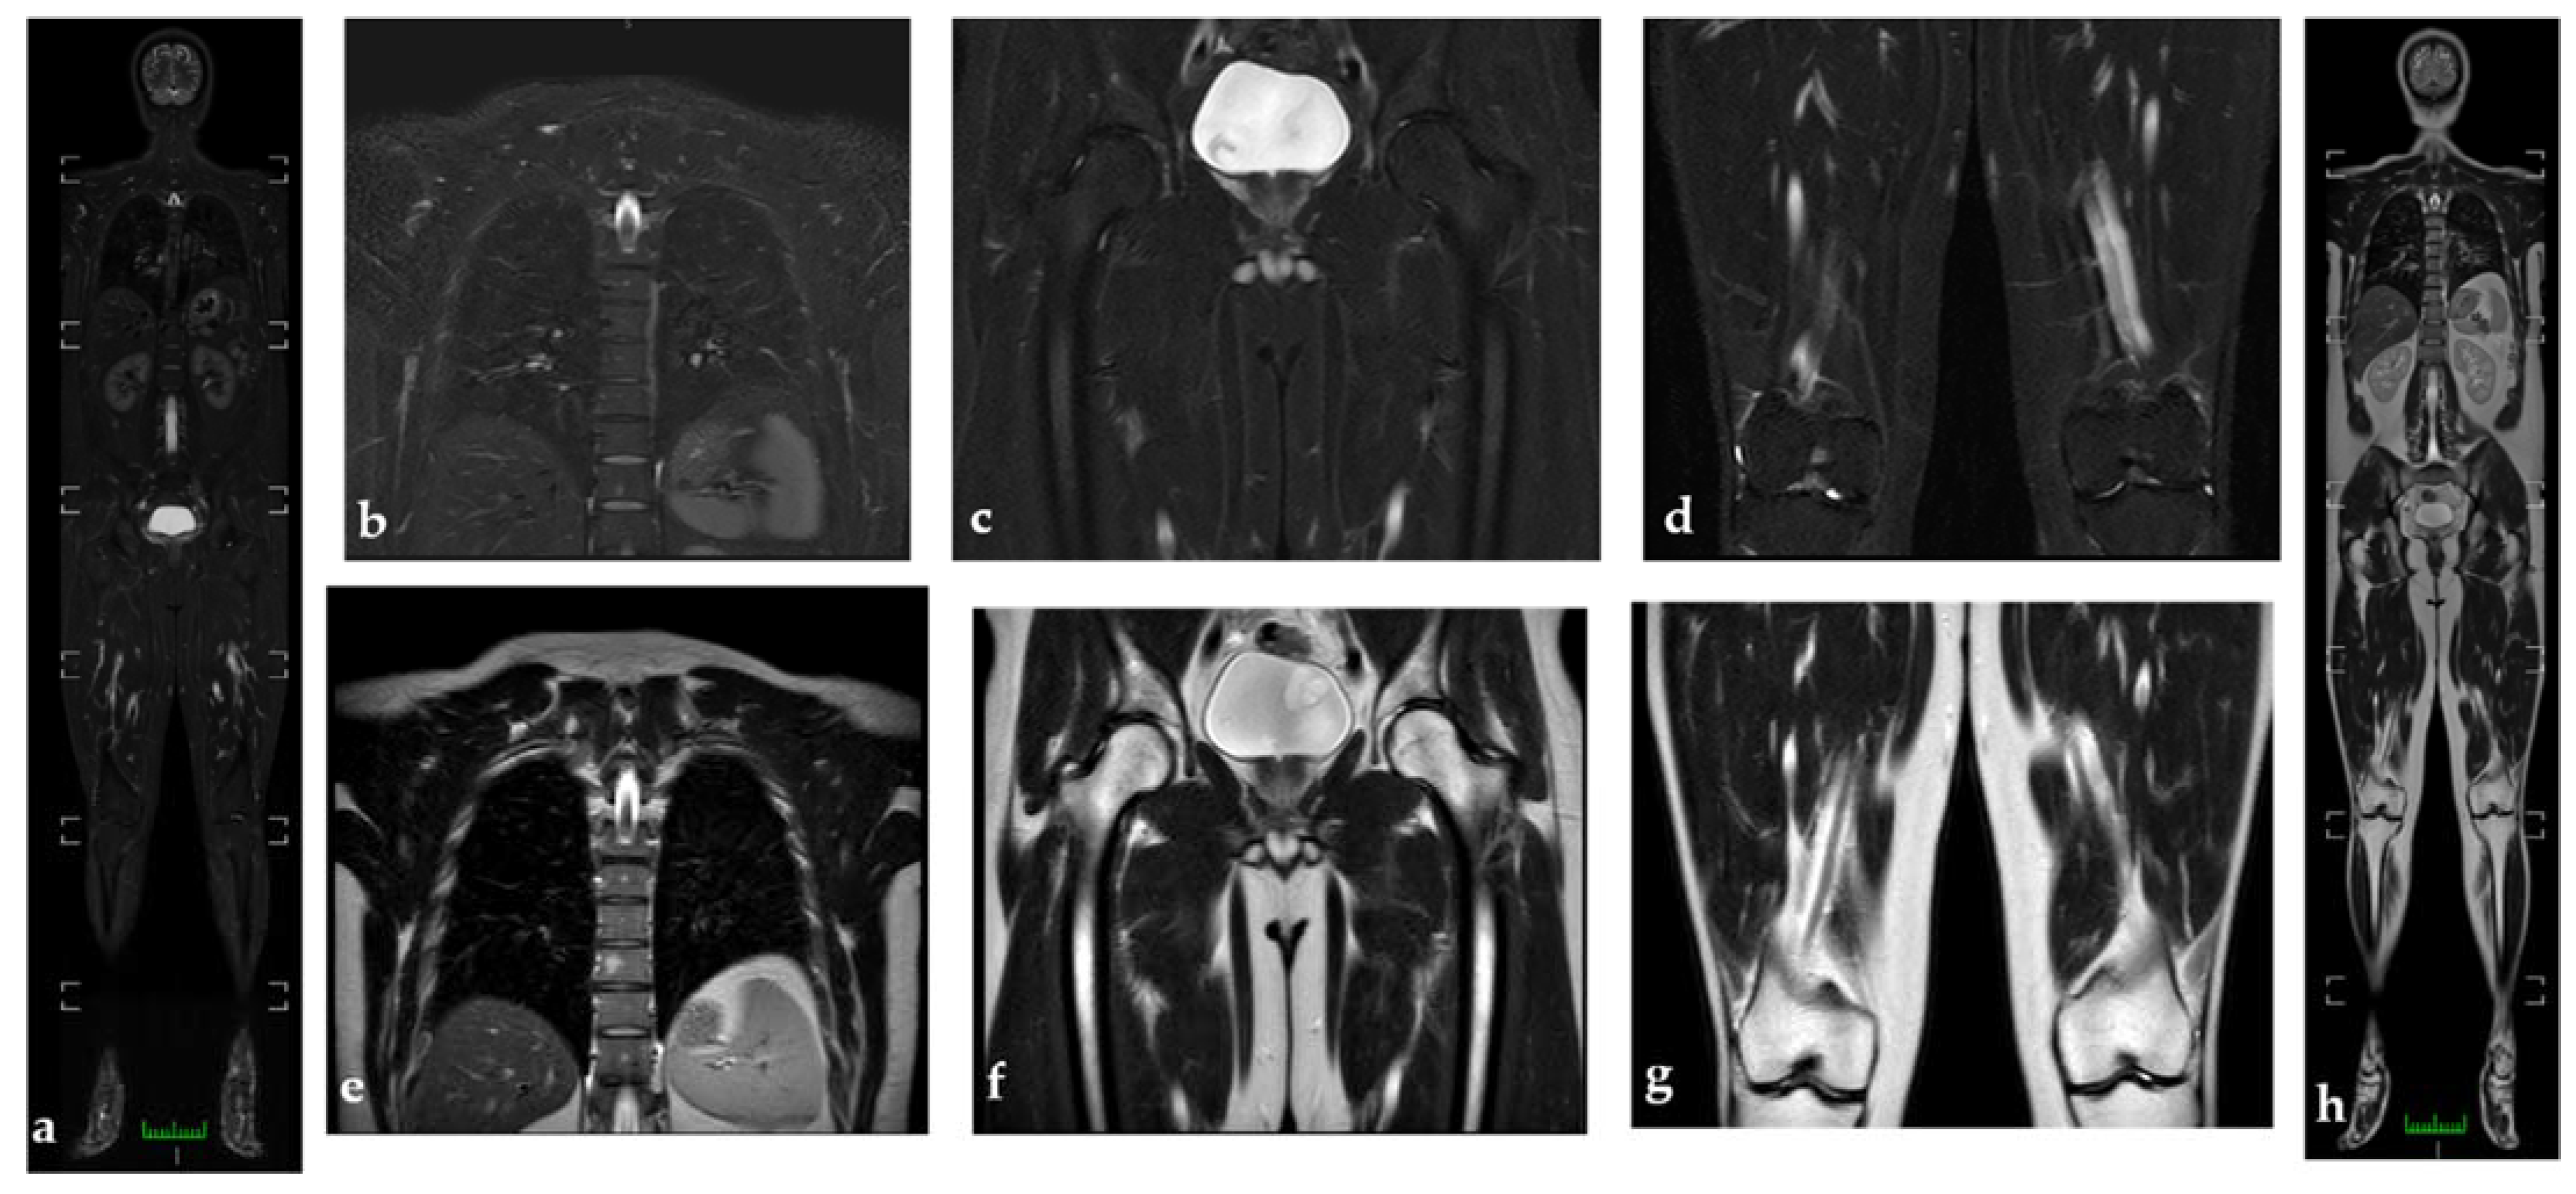

3.4. Muscular Multifocal Inflammatory Diseases

3.4.1. Antisynthetase Syndrome (ASS)

- The involved tissues including muscles, fasciae, and subcutaneous tissue. Muscular and subcutaneous tissue are both involved in DM and even the fasciae can be involved. In PM, we generally find isolated muscular edema.

- The topographical distribution of the lesions. In PM, shoulder and pelvic girdle are primarily involved.

- The portion of the muscle affected by the process (central, peripheric, or diffuse) [5].

3.4.2. IBM